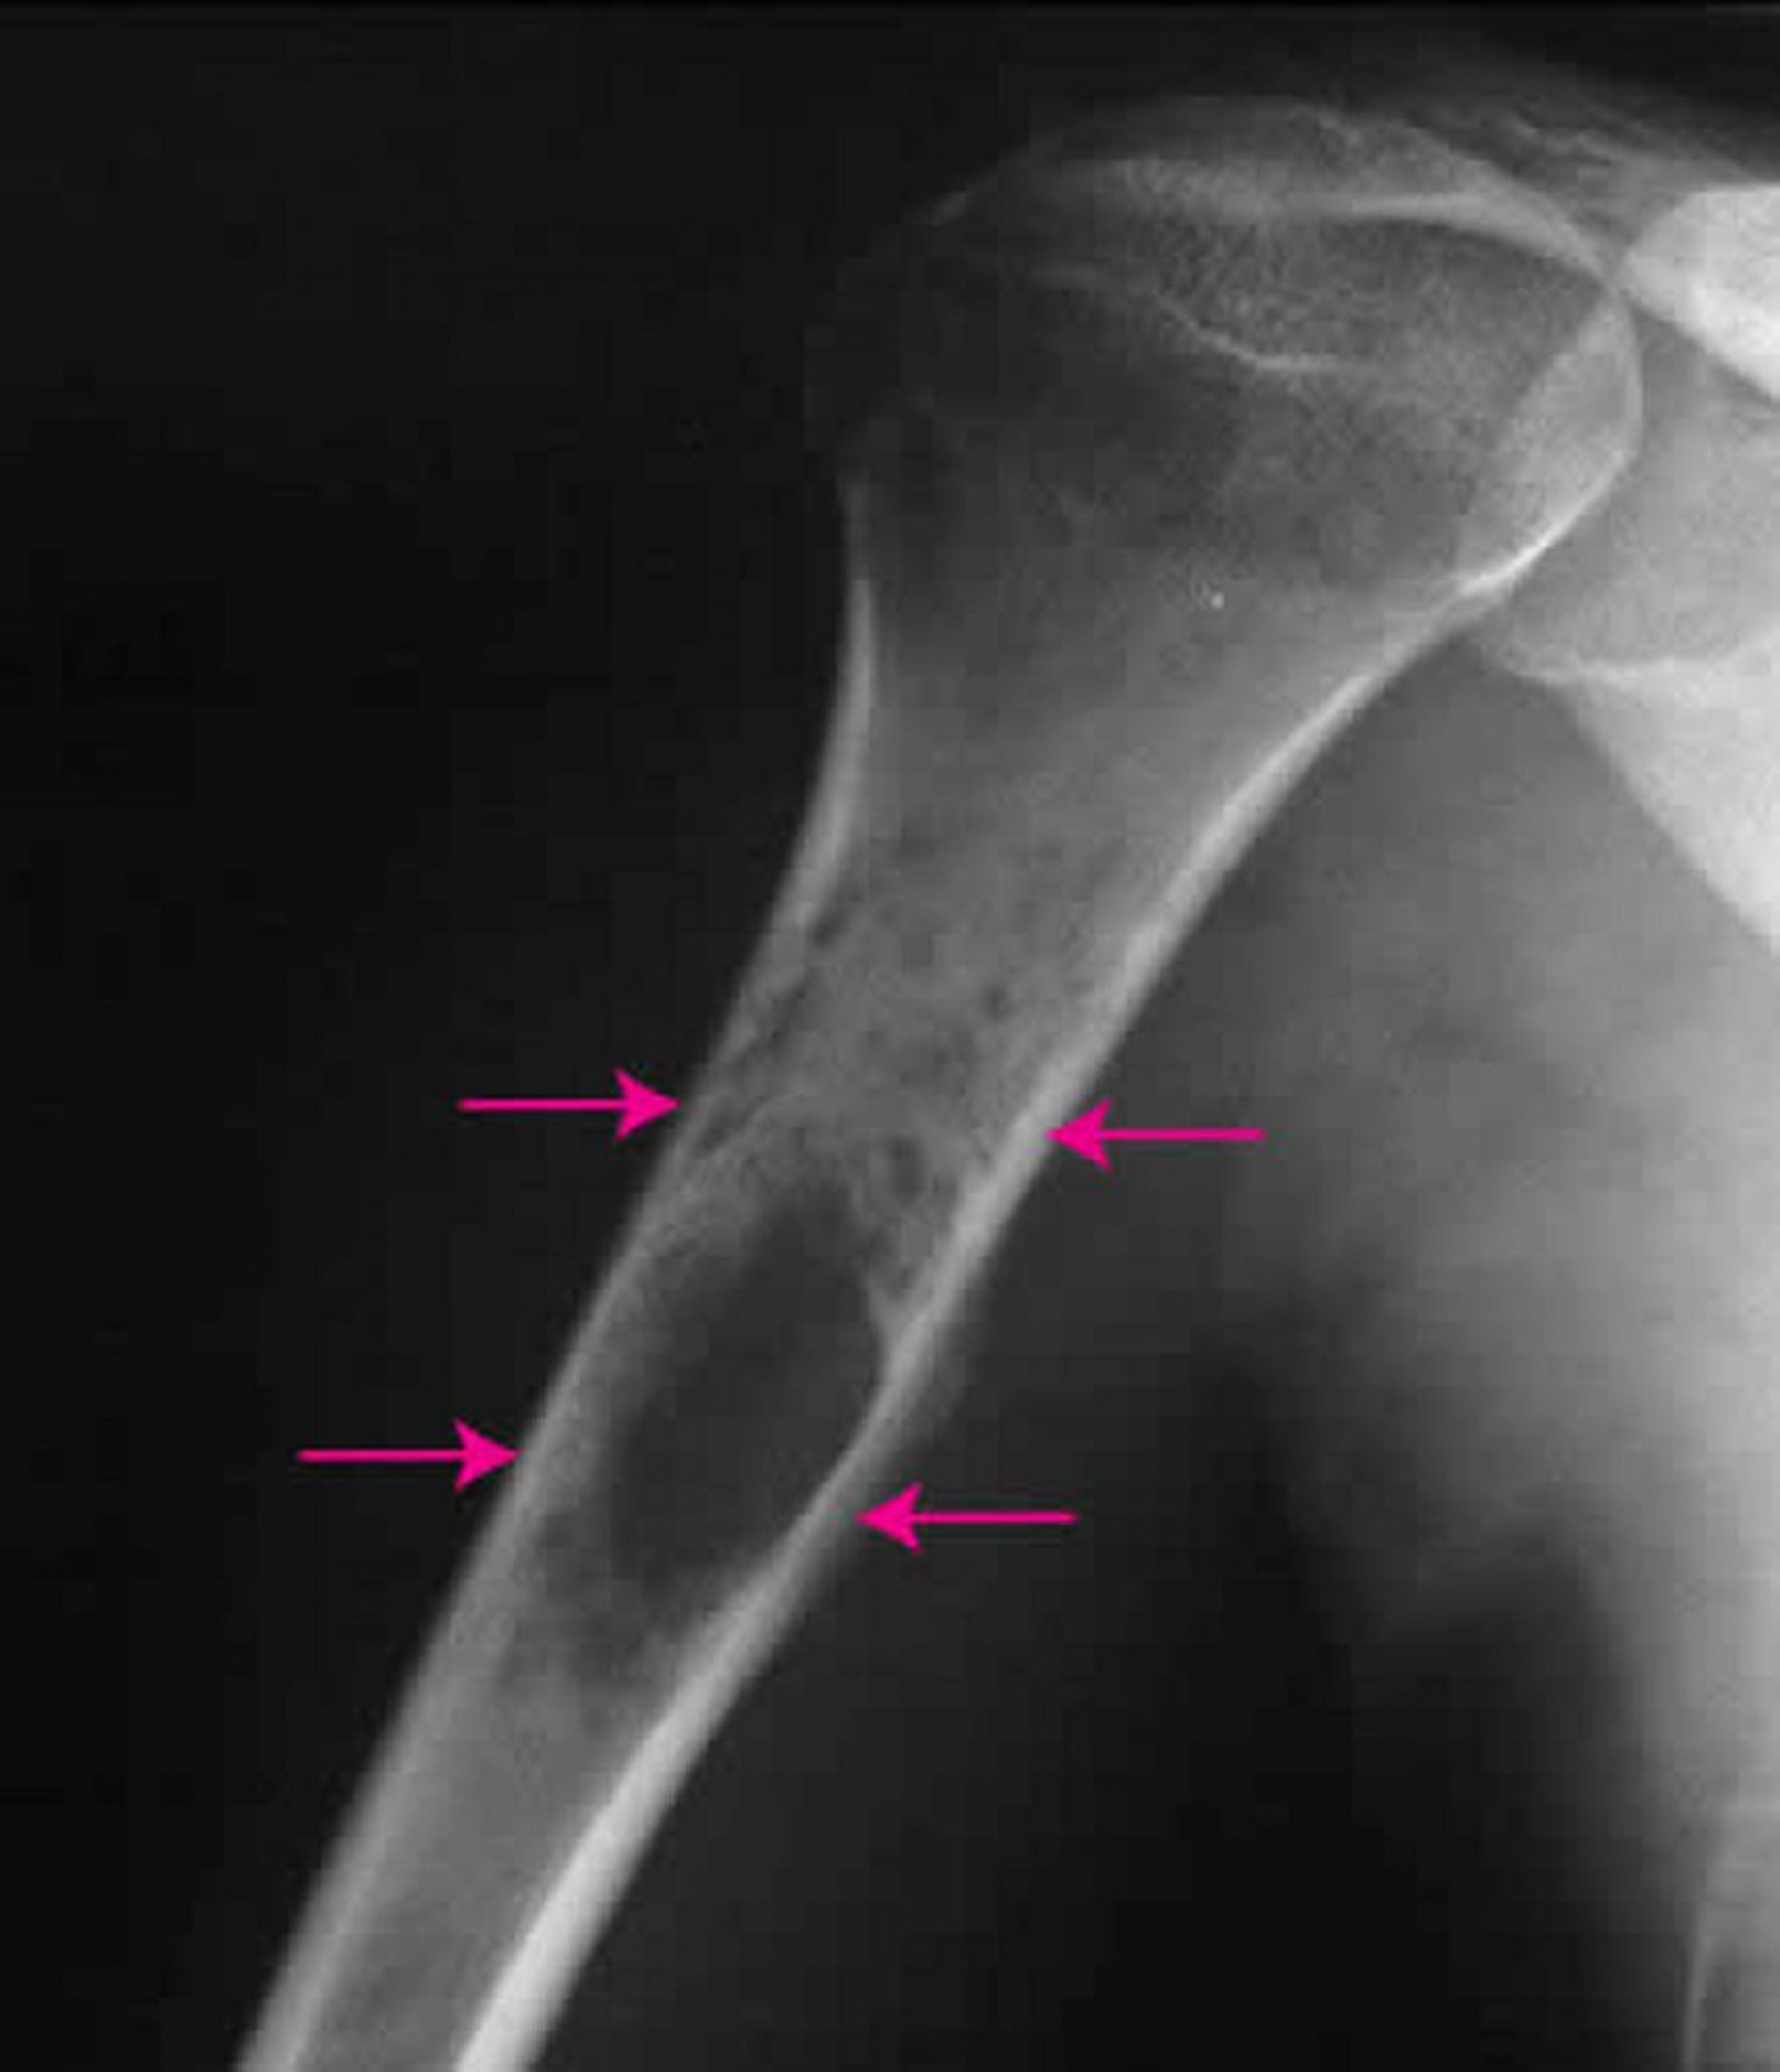

Radiografia della spalla che mostra un sarcoma di Ewing (frecce) all’interno dell’osso del braccio.

Per gentile concessione di Michael J. Joyce, MD e Hakan Ilaslan, MD.